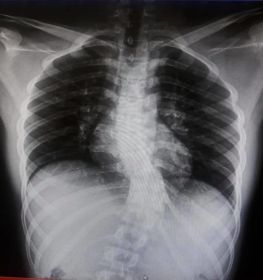

Skolyoz hastalığı omurgaların dizilimindeki düzensizlik ve yamukluktur. Çoğunlukla çocuklukta görülen hastalık yetişkinlerde de az da olsa görülebilir. Sağa sola omurgalardaki çıkıntıların zamanla omurilik eğriliği bir hale getirdiği hastalıkta erken tanı çok önemlidir. İster yetişkin isterse çocuk olsun erken teşhis sonucunda fizik tedavi yöntemi işe yarar. Hastalık özellikle kişilerin günlük yaşantılarını etkileyen olumsuzluklar yaşatan ve yaşam kalitesini düşüren bir rahatsızlıktır. Geç kalınmadan tedaviye başlanmalıdır.